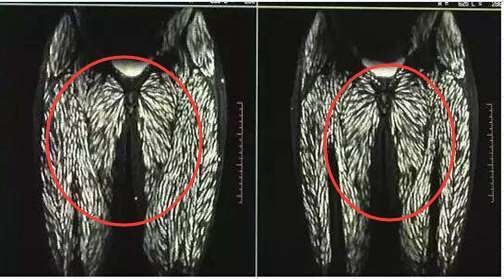

不料所有的檢查結果一出爐,馬上嚇壞了一旁看X光片的醫護人員,就連行醫多年的主治醫生都驚訝連連:簡直太不可思議了!原來從各種的各種影像檢查資料來看,眼球後方、大腿、腹壁、背部肌肉多個地方都長滿了寄生蟲,就連舌頭、臉部肌肉也有感染。抽血檢查後更進一步證實,婷婷的囊蟲抗體是陽性,屬於囊蟲感染。

▼畫面上布滿的白點,就是感染的寄生蟲。

由於婷婷生吃豬肉有一段歷史了,讓醫生發現到她的大腦裡有囊蟲鈣化現象,這表示裡面有囊蟲死去。而且患者眼球突出,視網膜出血,全身多處感染,會伴隨著癲癇發作,如此嚴重的狀況也是醫生第一次遇見。